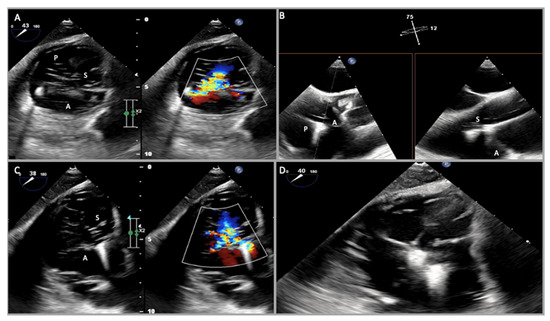

2.1. Two-Dimensional and Three-Dimensional Transthoracic and Transesophageal Echocardiography

3.1. Two-Dimensional and Three-Dimensional Transesophageal Echocardiography

4.1. Two-Dimensional and Three-Dimensional Transthoracic and Transesophageal Echocardiography